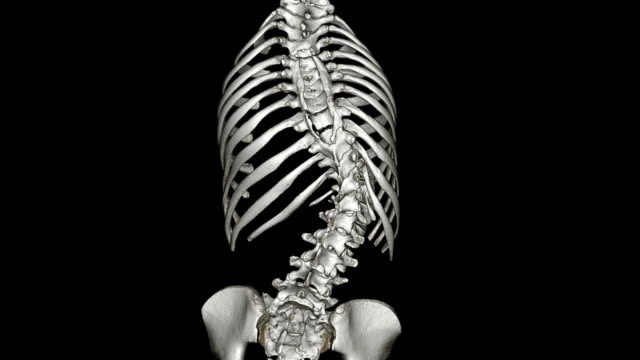

척추측만증은 허리가 옆으로 휘어진 상태를 나타내는 질환으로, 특히 청소년기에 많이 발생하는 허리의 변형이며 척추의 측만(옆으로) 휘어짐을 특징으로 합니다. 이 질환은 주로 10도 이상의 각도로 허리가 휘어질 때 측만증으로 분류됩니다.

척추측만증은 척추가 휘었다는 이야기 인데요. 많은 사람들이 이정도는 알고 있습니다.

하지만 조금 더 정확하게 어떤게 척추측만증인지 알지는 못합니다.